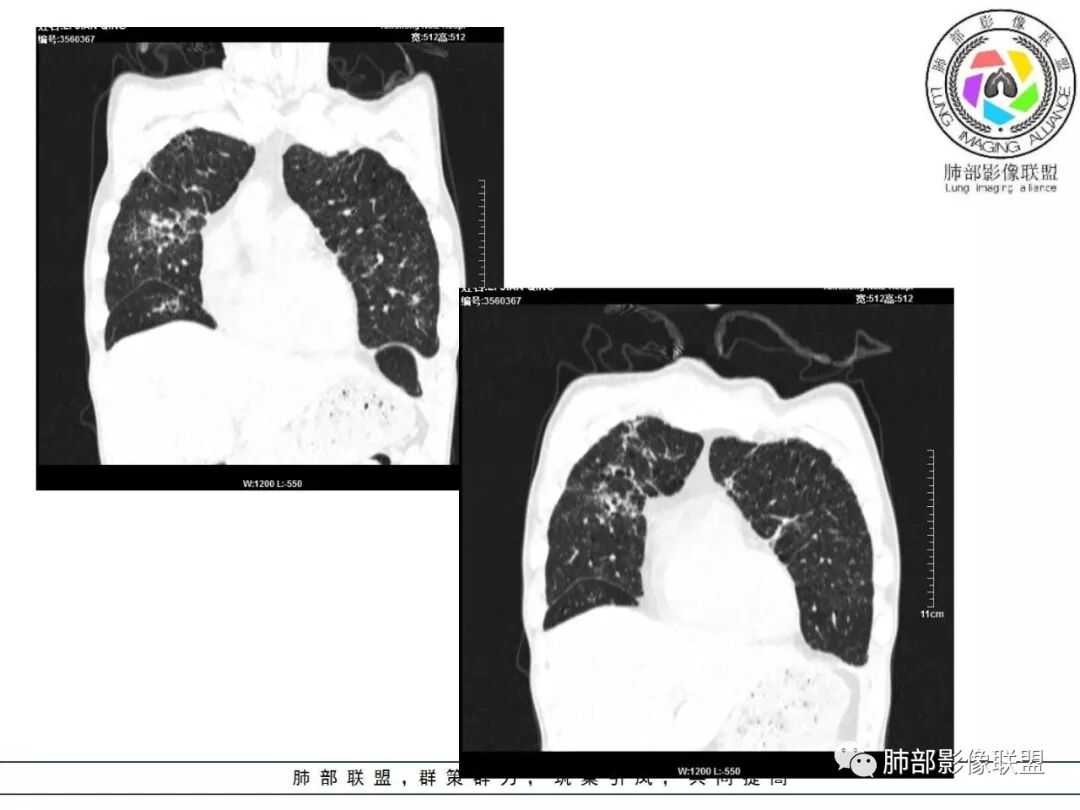

双肺间质性病变,中央间质增厚,胸膜下间质增厚,左侧胸膜肥厚,胸廓变小,肋间隙变窄。

对,大的支气管血管周围

胸部CT:两肺弥漫病灶,磨玻璃影,少许实变,部分累及胸膜,磨玻璃区可见囊?少许胸腔积液,两肺可见结节,支气管血管束增粗,小叶间隔增厚,支气管走形有扭曲扩张,可见纤维化。气肿、大泡。考虑:感染性病变,PCP?查下HIV,CD4,G等。鉴别结核、结缔组织病肺浸润。

胸部CT:两肺弥漫病灶,中央间质分布为主,部分位于胸膜及叶间裂旁,磨玻璃影,斑片影,部分实性结节,肺气囊,支气管血管束增粗,小叶间隔增厚,叶间裂不均匀增厚,支气管走形有扭曲扩张,可见纤维化、气肿、大泡。考虑:LIP加MALT。鉴别PLCH、PCP、结核、结缔组织病肺浸润。

病变一般沿血管支气管束分布或小叶分布,一般上肺多于下肺(这与常见继发性肺结核分布相若)。

2. 肺气肿背景(小叶中心性肺气肿);双肺多发病灶整体沿血管支气管束及胸膜下分布,以上叶及下叶背段分布为主,有实变及GGO,边界清楚,有树芽,小叶间隔及中央间质增厚,叶间裂见到多发结节,部分支气管不规则牵拉扩张,提示病灶纤维化明显,结合临床病史,考虑病灶为间质性感染,肺门及纵隔内有钙化淋巴结,小叶间隔结节,考虑淋巴道增值性疾病可能,综合常规要怀疑间质性肺结核。